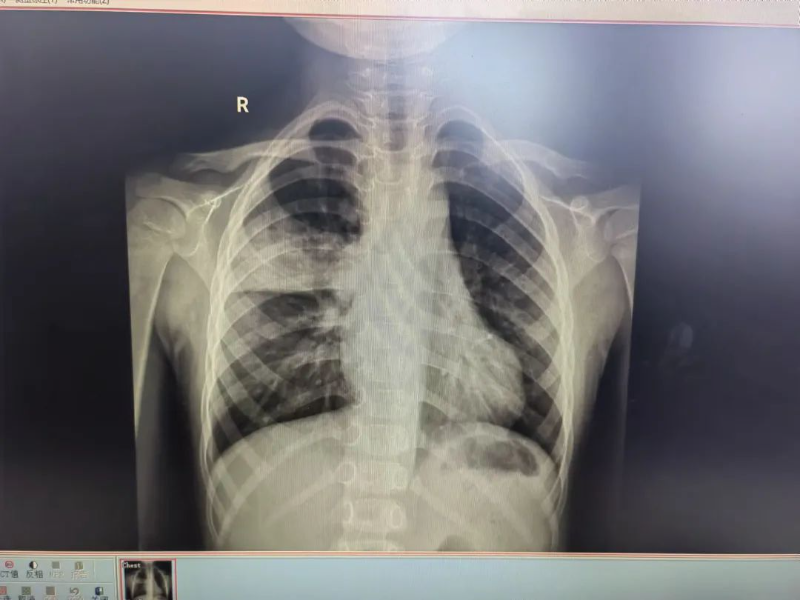

门诊胸片结果显示,帆帆的右上肺存在感染并伴有实变,结合其临床表现,门诊医生判断帆帆患上了儿童社区获得性肺炎,即刻安排他入住普儿科接受治疗。住院期间,普儿科副主任医师陈玲与龙斌每天轮流多次巡房查看帆帆的病情,并耐心细致地诊治。陈玲为他制定了个性化的治疗方案,时刻关注其病情变化,确保治疗方案的有效性和安全性。

治疗前(左)、后(右)胸片对比